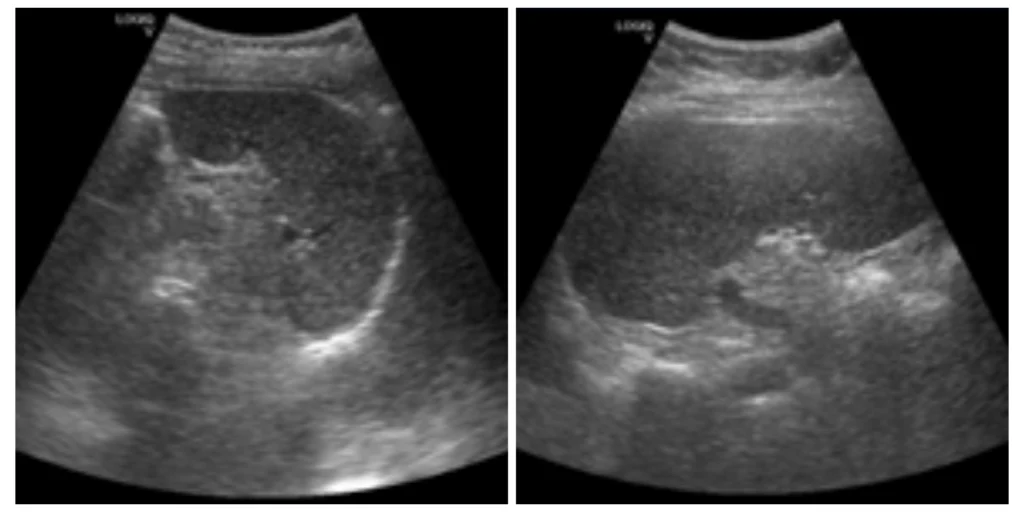

Analisis Pengaruh Variasi Frekuensi Transduser Convex Terhadap Kualitas Citra Ultrasonografi Lien Kasus Obesitas

VOKASI NEWS – Analisis pengaruh variasi frekuensi transduser convex terhadap kualitas citra ultrasonografi lien pada pasien obesitas. Obesitas menjadi salah satu isu kesehatan global yang terus meningkat dari tahun ke […]